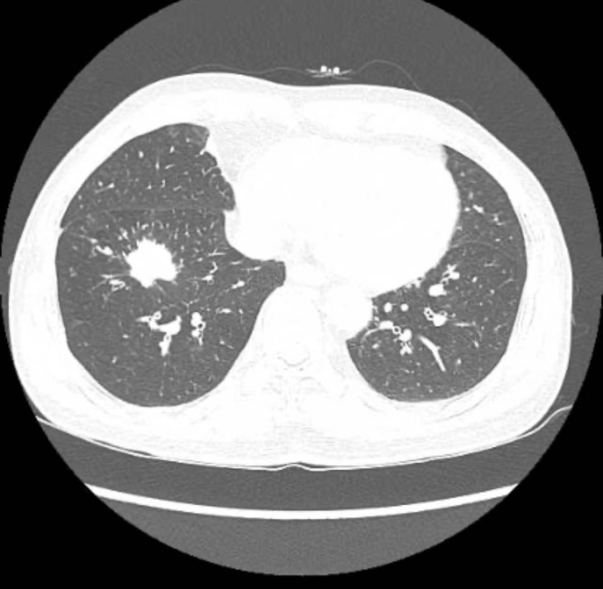

今年57岁的王先生,因咳嗽来到中南大学湘雅二医院桂林医院临桂院区呼吸与危重症医学科就诊。经过胸部CT扫描检查,放射科医师发现王先生右下肺有一个硬币大小的肿块。针对此情况,医院胸外科、呼吸与危重症医学科、放射科组成的肺结节多学科(MDT)诊疗团队对患者的病情进行了深入讨论。

CT结果显示患者右下肺病变

经检查、分析和评估,专家团队考虑王先生的肺部结节极有可能是原发性肺癌,应当尽早进行外科介入,接受微创手术治疗。因王先生家住临桂区,参与会诊的中南大学湘雅二医院派驻专家、中南大学湘雅二医院桂林医院胸外科执行主任梁恒星副教授建议患者直接在临桂院区新启用的手术室接受手术,免去在叠彩、临桂两区奔波的不便。患者及家属听闻这一消息,欣然接受了梁恒星副教授的建议。